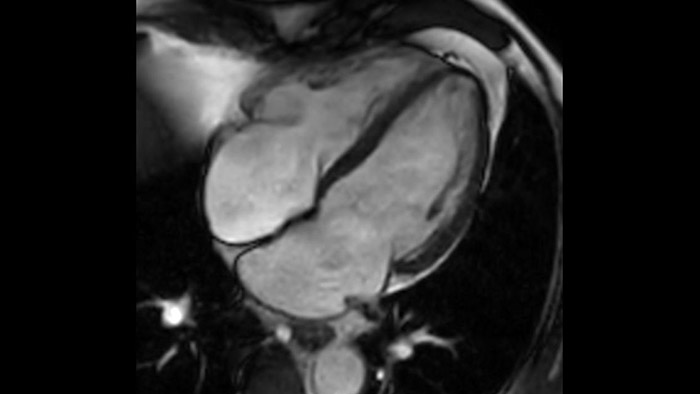

Diagnostic and prognostic utility of cardiac MR is increasing. Assess the anatomy and function of the heart using cine acquisitions, acquire information about perfusion and viability of the cardiac tissue, visualise potential edema with black blood sequence, access and even quantify tissue characterisation with CardiacQuant.

IntelliSpace Portal MR Caas5,6 Strain7 assists in patient diagnosis and monitoring by providing global strain parameters such as global longitudinal strain (GLS), global circumferential strain (GCS), and global radial strain (GRS), using short and long axis MR images, as well as describing the myocardium deformation- such as shortening, thickening, and lengthening during the cardiac cycle.